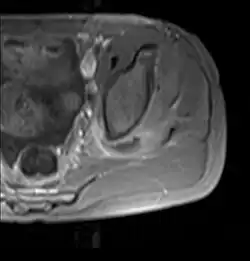

Axial T1 weighted fat suppressed post IV gadolinium contrast enhanced MRI image showing a mutliloculated bacterial abscess in the left gluteal muscle which grew Staphylococcus aureus (methicillin sensitive) thought to be due to tropical pyomyositis.

Coronal fat suppressed post contrast image showing a multiloculated bacterial abscess in the left gluteus minimus muscle due to tropical pyomyositis.

Coronal T2 weighted fat suppressed image showing a multiloculated fluid collection in the left gluteal musculature due to tropical pyomositis in a 12-year-old boy.